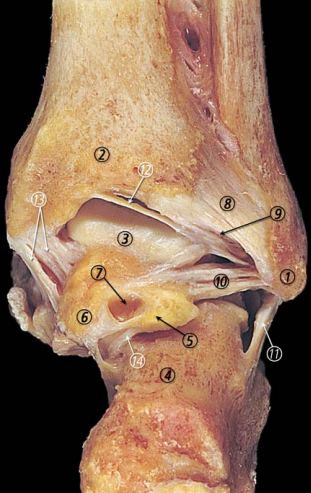

解剖